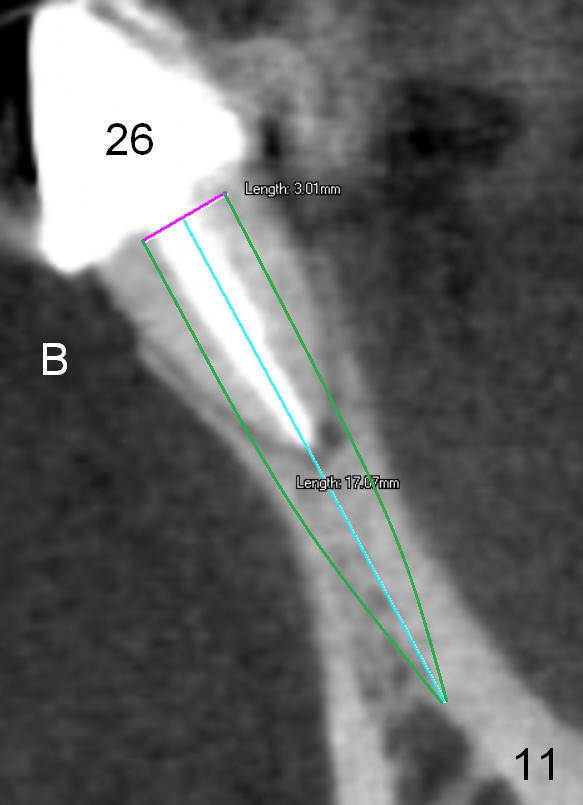

Fig.7 shows these two one piece implants immediately prior to cementation of the FPD (Fig.8). They are much more parallel to each other after prep, as compared to Fig.6. Fig.9 shows apparent bone growth around #24 implant (at the crest) 6,9 months post cementation and surgery, respectively. Orthodontic treatment will incorporate the fixed partial denture. Fig.10 shows that bone grows coronally (arrow) to cover 3 threads (from #6 thread to #3) at the site of #24 one year after functioning. There is mild buccal gingival infection involving #26 retainer. Preop CBCT is reviewed to determine whether it is related to potential thread exposure. It appears that at the sites of #24 (Fig.13,14) and 26 (Fig.11,12), 2.5 mm implant is more appropriate for the narrow ridge than 3.0 mm one. In fact, periimplantitis develops at #26 two years of absence of perio maintenance (because of atrial fibrillation with blood thinner; Fig.15, 3 years 7 months post cementation). Periimplantitis persists 4.5 months later. Although water pik is purchased, it is not used often because of low blowing force. If needed, remove the FPD atraumatically. Unwind the implant, clean the coronal threads with Titanium brush or remove the exposed threads and replant the implant with bone graft.

The infection persists at #26 four years 8 months post cementation (Fig.16 *). CBCT is taken. In fact the implant at #26 was placed lingual (Fig.17), while that at #24 buccal (Fig.20). The 2nd option is to remove the implant at #26 and place a 2 mm one at #25 (Fig.18,19). Fabricate a 3-unit cantilever FPD. Take 5x5 cm CT with 1.2 mm drill in place for 10 mm. Change the trajectory and position if necessary.